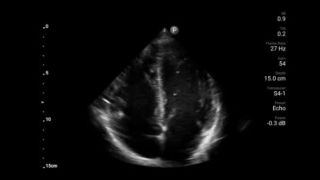

Every second counts in cardiac care

Heart attack patients need immediate care. Lumify's cardiac presets can help patients get diagnosed faster to improve their outcomes.

Lumify S4-1 broadband phased array transducer

• 4 to 1 MHz extended operating frequency range • 2D, color Doppler, M-mode, advanced XRES and multivariate harmonic imaging • High-resolution imaging for abdominal and cardiac applications: Cardiac, OB/GYN, Lung, Abdomen and FAST imaging preset optimizations Lumify aids life-saving technology in prehospital setting

Integrating Lumify into a resuscitation environment